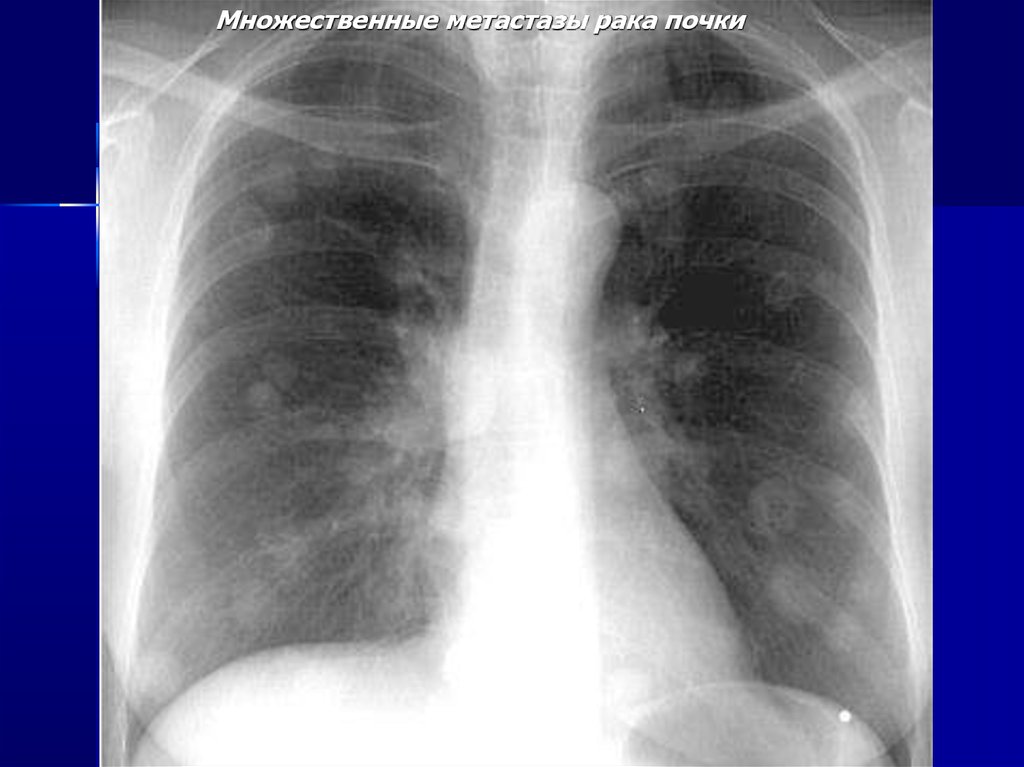

Множественные метастазы рака почки